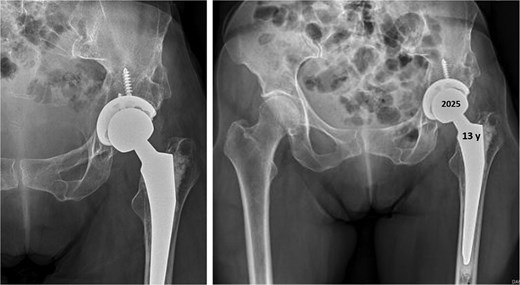

Thirteen years after THA, the 76-year-old patient continued to have a stable asymptomatic hip. Hip radiographs showed unchanged and stable positioning of the acetabular cup and femoral stem, with no measurable subsidence or radiolucent lines around the components (Fig. 4).

Postoperative anteroposterior radiographs of the pelvis 13 years after the THA, showing mechanical stability of the prosthesis with no evidence of loosening. No signs of osteoarthritis are present in the right hip (Tönnis Grade 0).